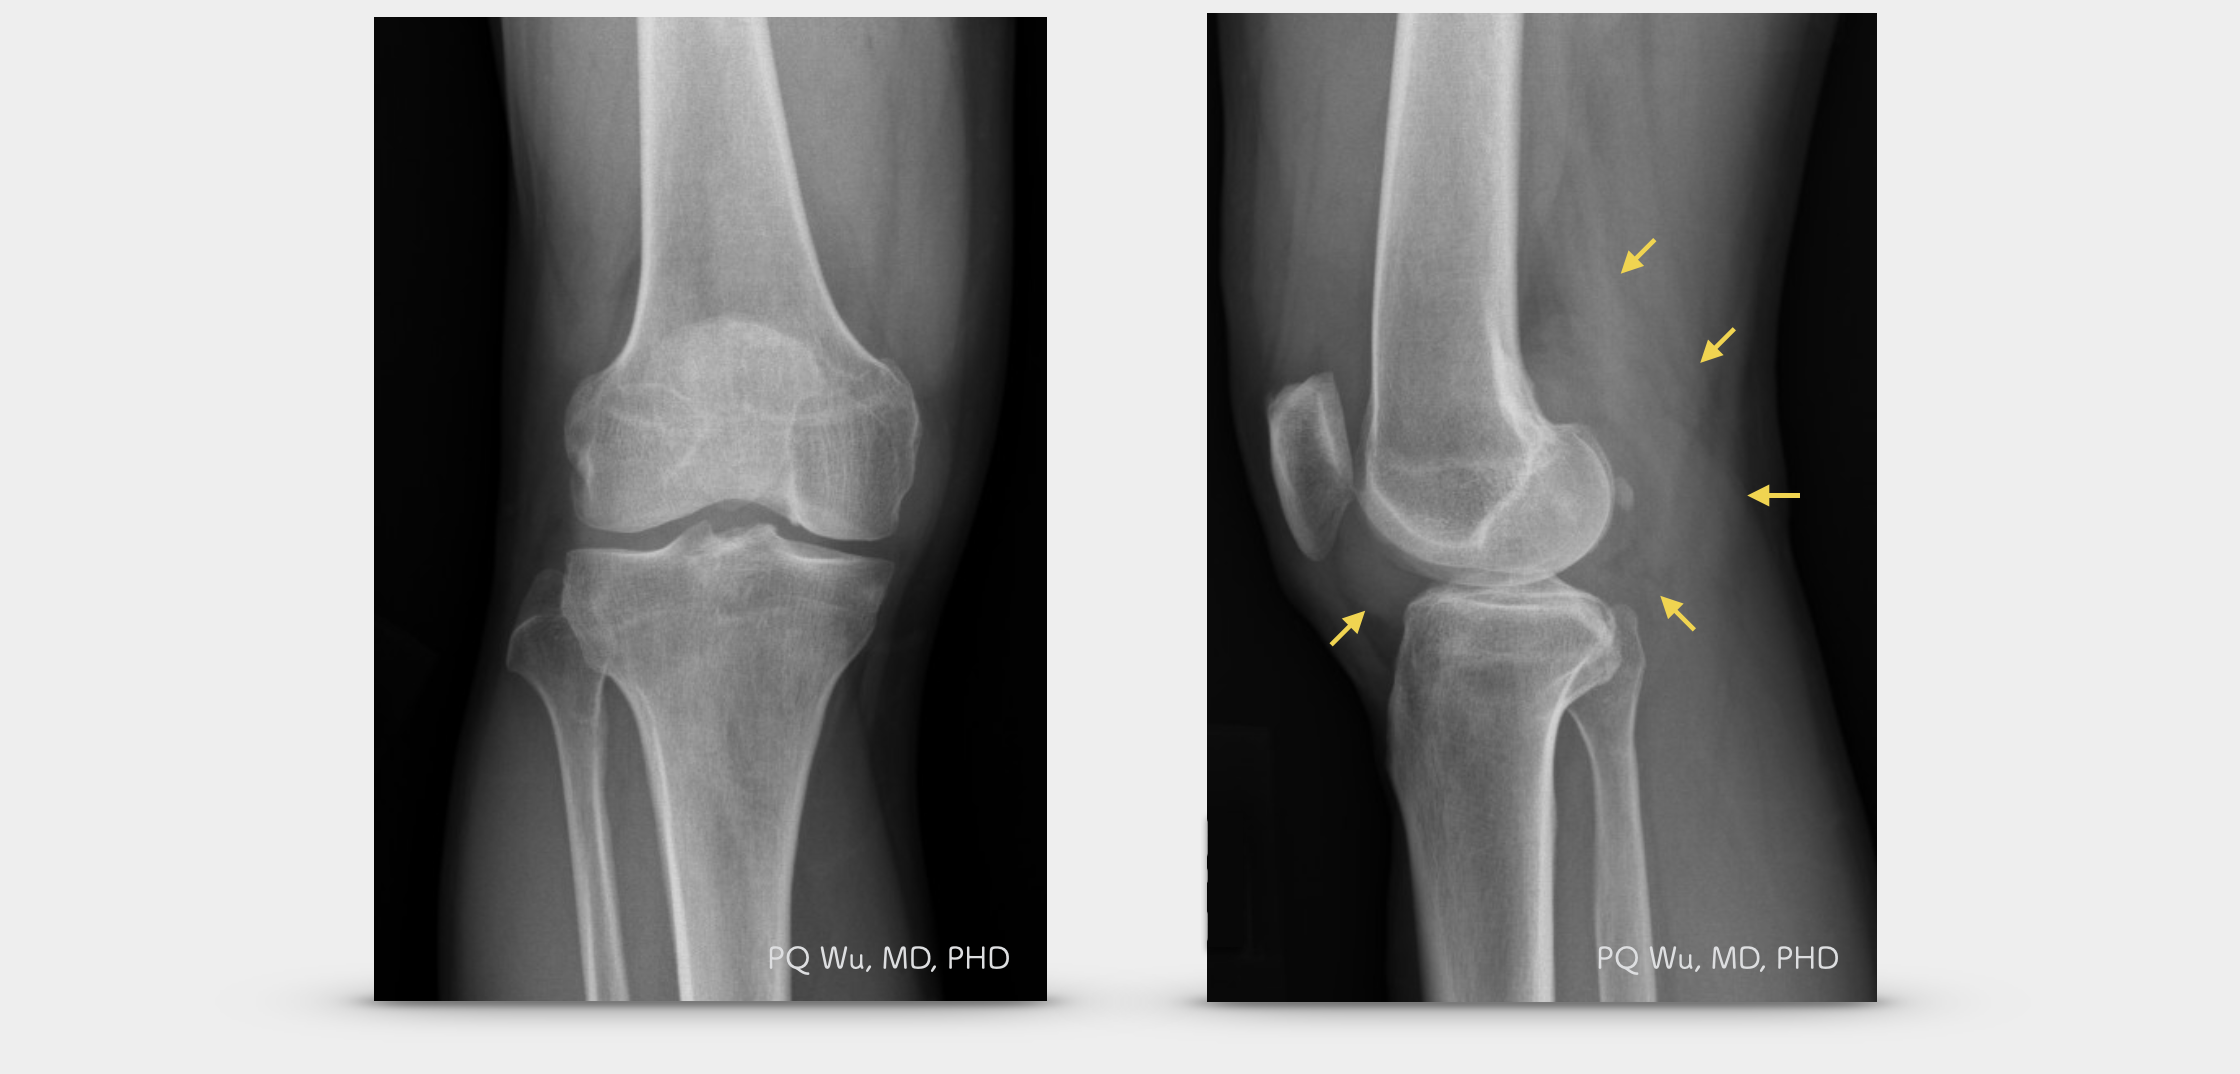

在X光的影像之中,發生在膝關節之腱鞘巨細胞瘤可以見到軟組織腫脹的現象,較少見到骨骼組織的破壞。但若是發生在髖關節附近的腱鞘巨細胞瘤,則常會見到合併骨骼結構的破壞,而有時不易與缺血性股骨頭壞死做區分。

46歲男性,右膝腱鞘巨細胞瘤(X光)